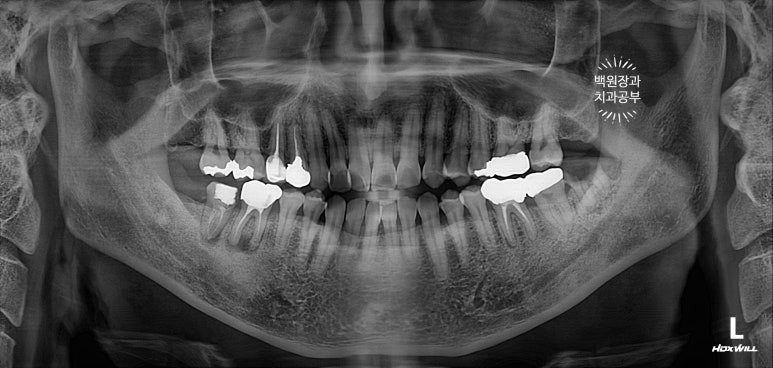

치과용 파노라마 엑스레이를 보니 오른쪽 아래 두번째 큰어금니와 왼쪽 아래 사랑니가 머리가 부러져 있네요.

그 중 오른쪽 아래 어금니는 신경치료를 하셨던 이빨인데, 이차 충치가 심해서 부러진 모양입니다.